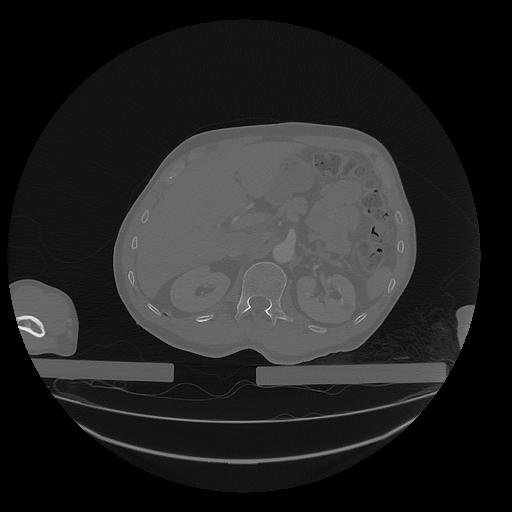

31 PULMON,CE,Vol,1.0,PULMON,,